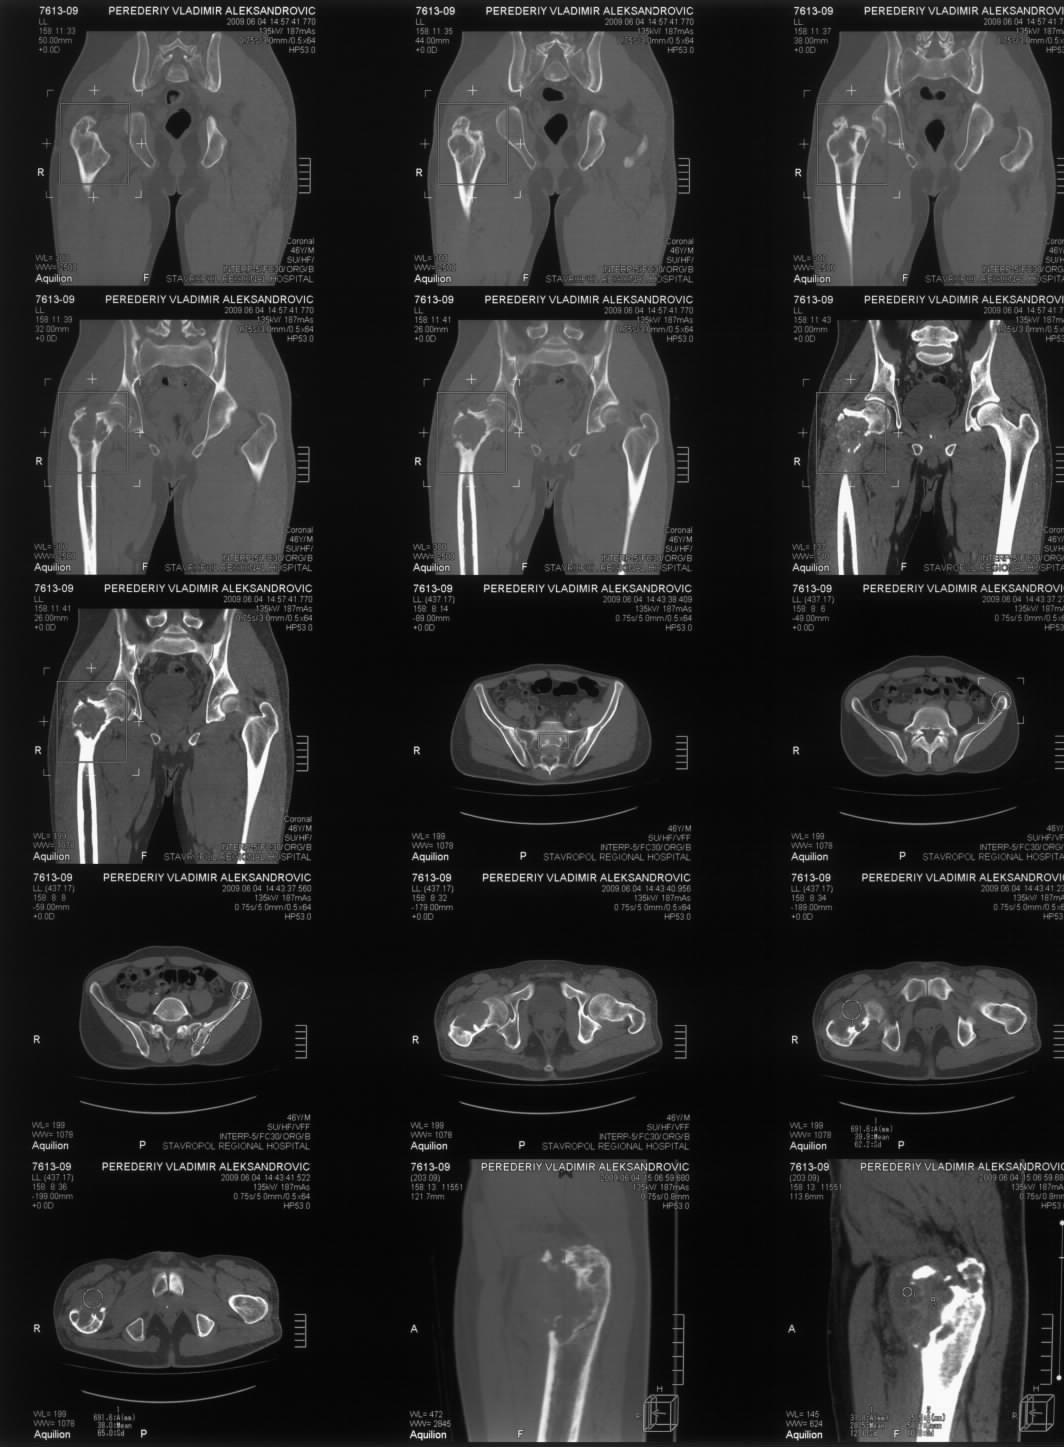

Диагноз: Ангиосаркома проксимального отдела правой бедренной кости. Патологический перелом шейки бедренной кости. Множественные метастазы в легкие, позвоночник, ребра, кости таза.

Считает себя больным с 2005 года, когда впервые появились боли в правом тазобедренном суставе с иррадиацией в поясничную область. Лечился по месту жительства по поводу поясничного остеохондроза, люмбоишиалгии. Отмечает постепенное усиление болей в области правого тазобедренного сустава. С августа 2007 года появилась хромота. В 2008 году была выполнена рентгенография тазобедренного сустава, выявлен патологический очаг в проксимальном отделе бедренной кости. Консультирован онкологом. Обследовался стационарно в травматолого-ортопедическом отделении №1 ГУЗ «СККЦ СВМП». Была выполнена операционная биопсия. Заключение: «наиболее вероятна картина гемангиоэндотелиомы с явлениями пролиферации и атипии». Для дальнейшего лечения был направлен в РОНЦ им. Н.Н.Блохина РАМН. Повторно была выполнена операционная биопсия с иммуногистохимическим исследованием материала. Заключение: «морфологическая картина более всего соответствует ангиосаркоме». Получил курс лучевой терапии. Планировалась повторная госпитализация для органосохраняющего оперативного лечения. Однако до настоящего времени госпитализация не состоялась.

31.05.09 упал дома с высоты собственного роста. Появились сильные боли в правом тазобедренном суставе. Самостоятельно обратился в ГУЗ «СККЦ СВМП». При клиническом обследовании и рентгенографии был диагностирован патологический перелом шейки бедренной кости.Объективно:

Интересно как онкологи оценивают вероятную подолжительность жизни, если более полугода, то наверное можно предложить биполярный онкологический протез. Для обсуждения не хватает снимков бедра на всю длину, и более подробной КТ ацетабулюма.

По этому пациенту тактика, видимо, должна зависеть от онкологического прогноза. Если онкологи оценивают ожидаемую продолжительность жизни больше 2-3 лет, то ориентировааться на онкологический протез с резекцией очага. Если прогноз хуже, то сделать остеосинтез гамма гвоздем без вмешательства на очаге.

Судя по КТ опухоль кроме шейки захватила большой трохантер и частично головку бедра. На мой взгляд, даже самое удачное расположенние винтов гвоздя не позволит больному полностью наступать на ногу. Протез же позволит больному максимально улучшить качество оставшейся жизни с раннего послеоперационного периода.